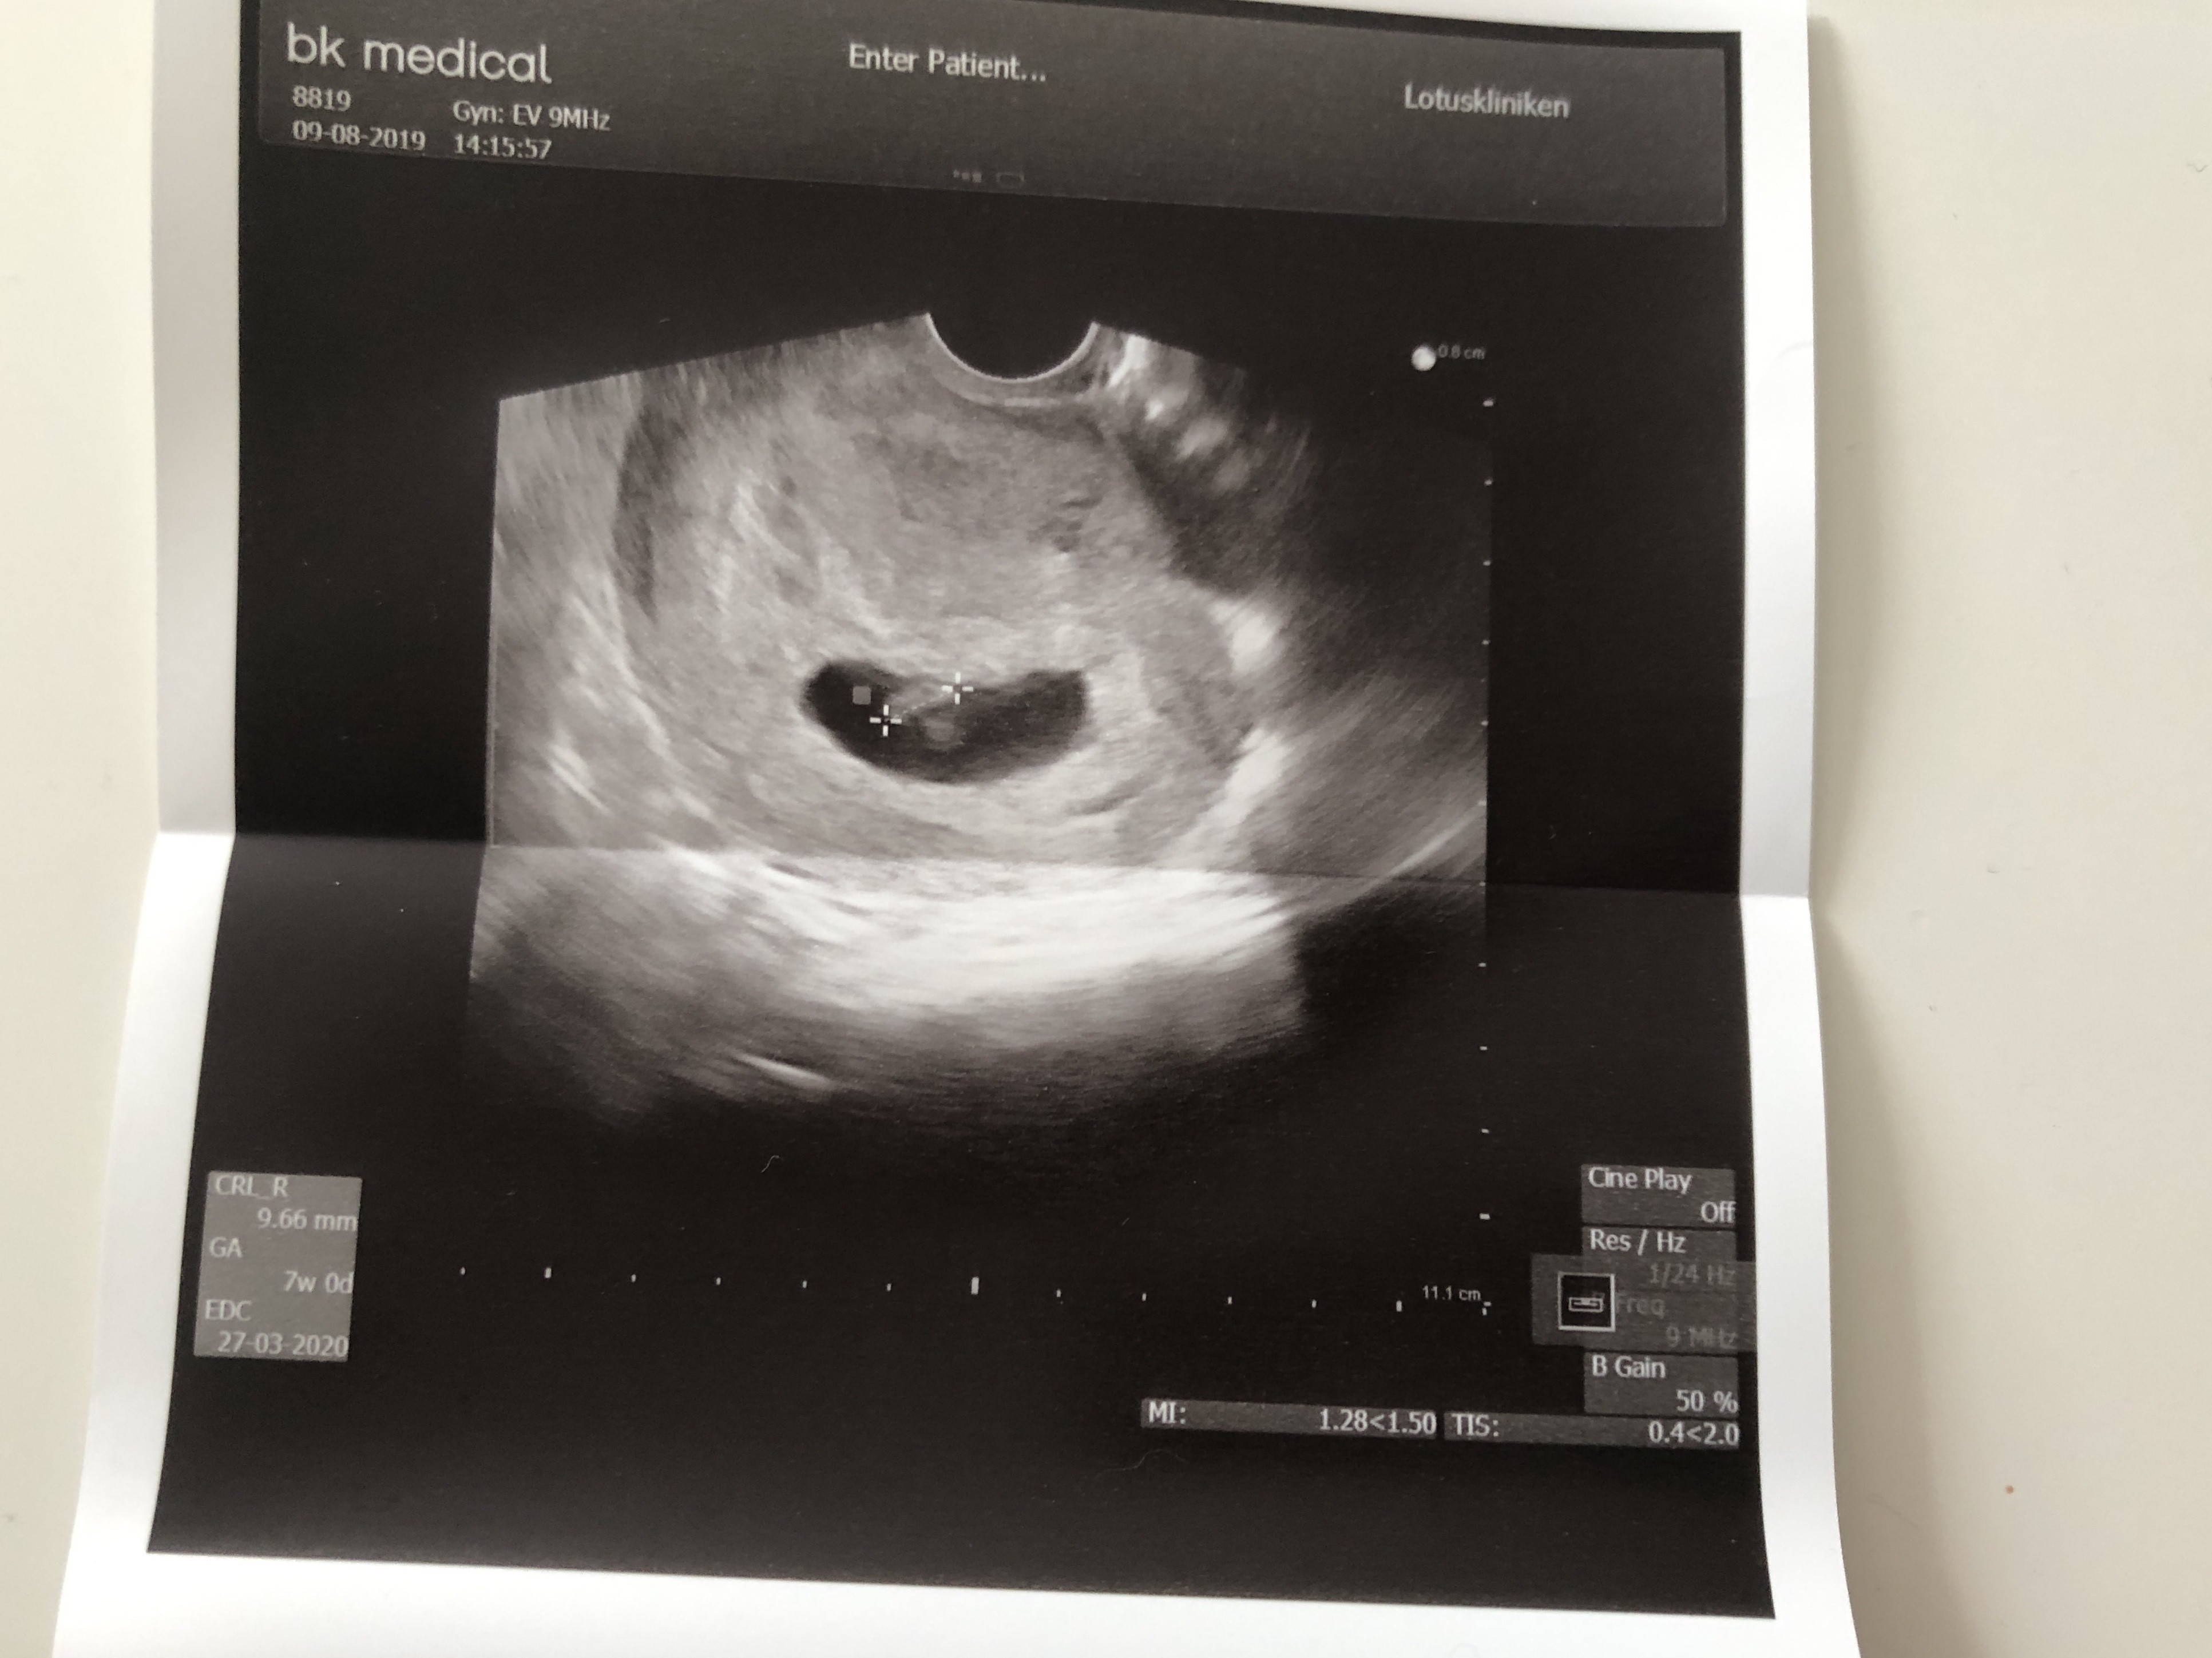

Dziewczyny ja dzis tez pojechalam zrozpaczona na usg. W jajnikach tak mnie swidrowalo az czasem zginalo w pol. Juz tak mam od niedzieli. Niby juz nie plamie ale dzis jakies takie dziwne pomaranczowe plamienie z jakims sluzem... Panika! Ogolem caly czas jestem spanikowana. Na całe szczęście dzidzia żyje i ma się dobrze! Ma juz ponad 2 cm

zbadal mi jajniki i mowi, ze w porzadku a to naturalna czynnosc skurczowa macicy. Chyba nie zasne spokojnie dopóki nie znajde sie w 2-gim trymestrze. Powodzenia dla Was wszystkich!